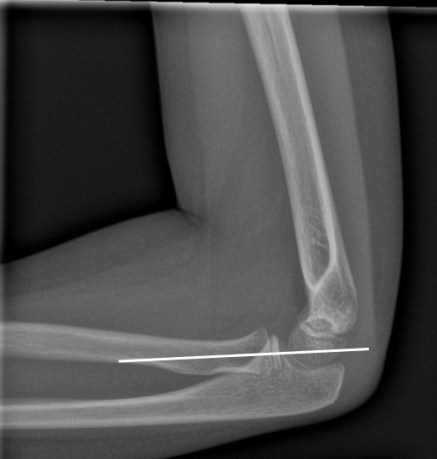

2. Radio-Capitellar Line: This goes across the joint, and is hence useful to detect dislocation.

It is drawn through the neck of the radius and it should pass through the capitellum (not necessarily bisect the capitellum). This relationship holds true in all views. If it does not pass through the capitellum, it implies that the radius is dislocated.